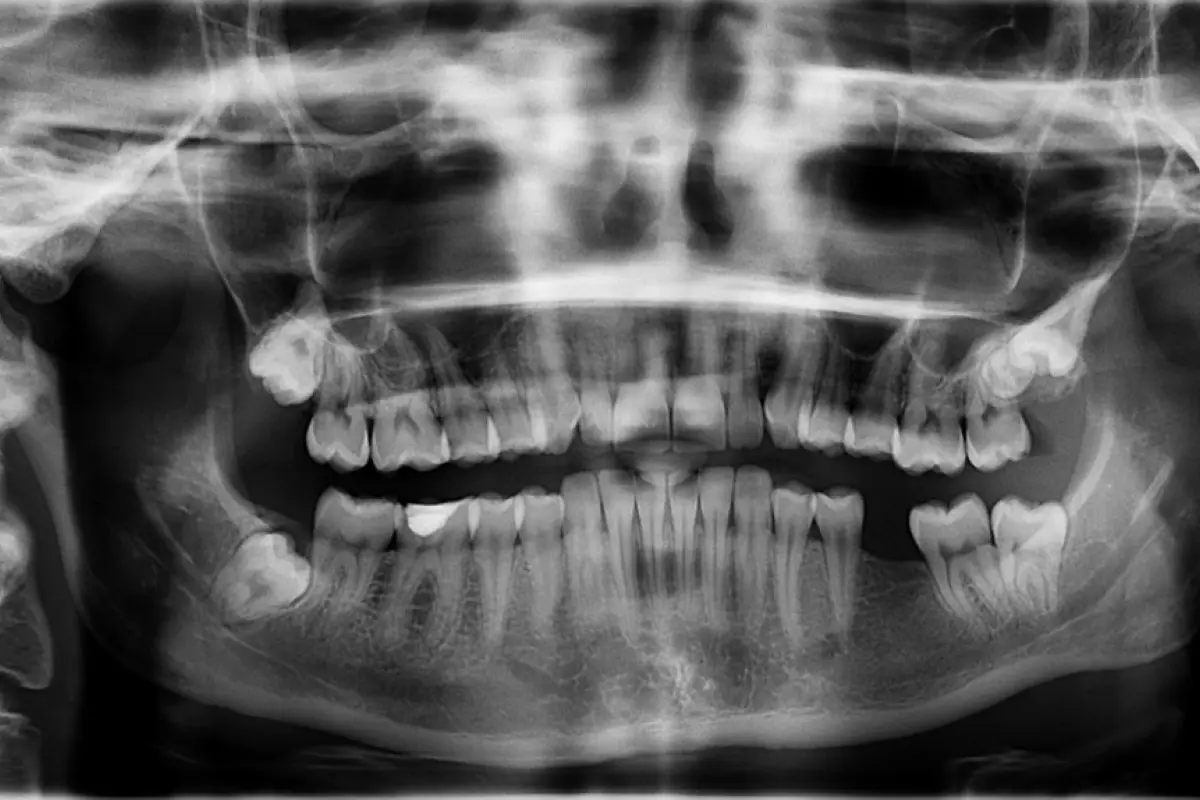

Los estudios radiológicos revelaron una masa de aproximadamente 200 gramos ubicada en la mandíbula. El Dr. Senthilnathan, quien lideró el equipo de cirugía oral y maxilofacial, identificó la condición como un "odontoma compuesto", un tipo de tumor beningo que afecta el desarrollo dental. "La especie de tumor que detectamos impidió el crecimiento permanente de los molares en el niño en el lado afectado", afirmó el cirujano tras la intervención.

Este diagnóstico fue respaldado por imágenes médicas que mostraban numerosos dientes rudimentarios agrupados en un tejido con forma de bolsa, una presentación bastante inusual en la literatura médica. La magnitud del hallazgo sorprendió incluso a los médicos más experimentados. Dentro de la bolsa, los cirujanos encontraron 526 pequeños dientes, con tamaños que oscilaban desde 0,1 milímetros hasta 15 milímetros de longitud.